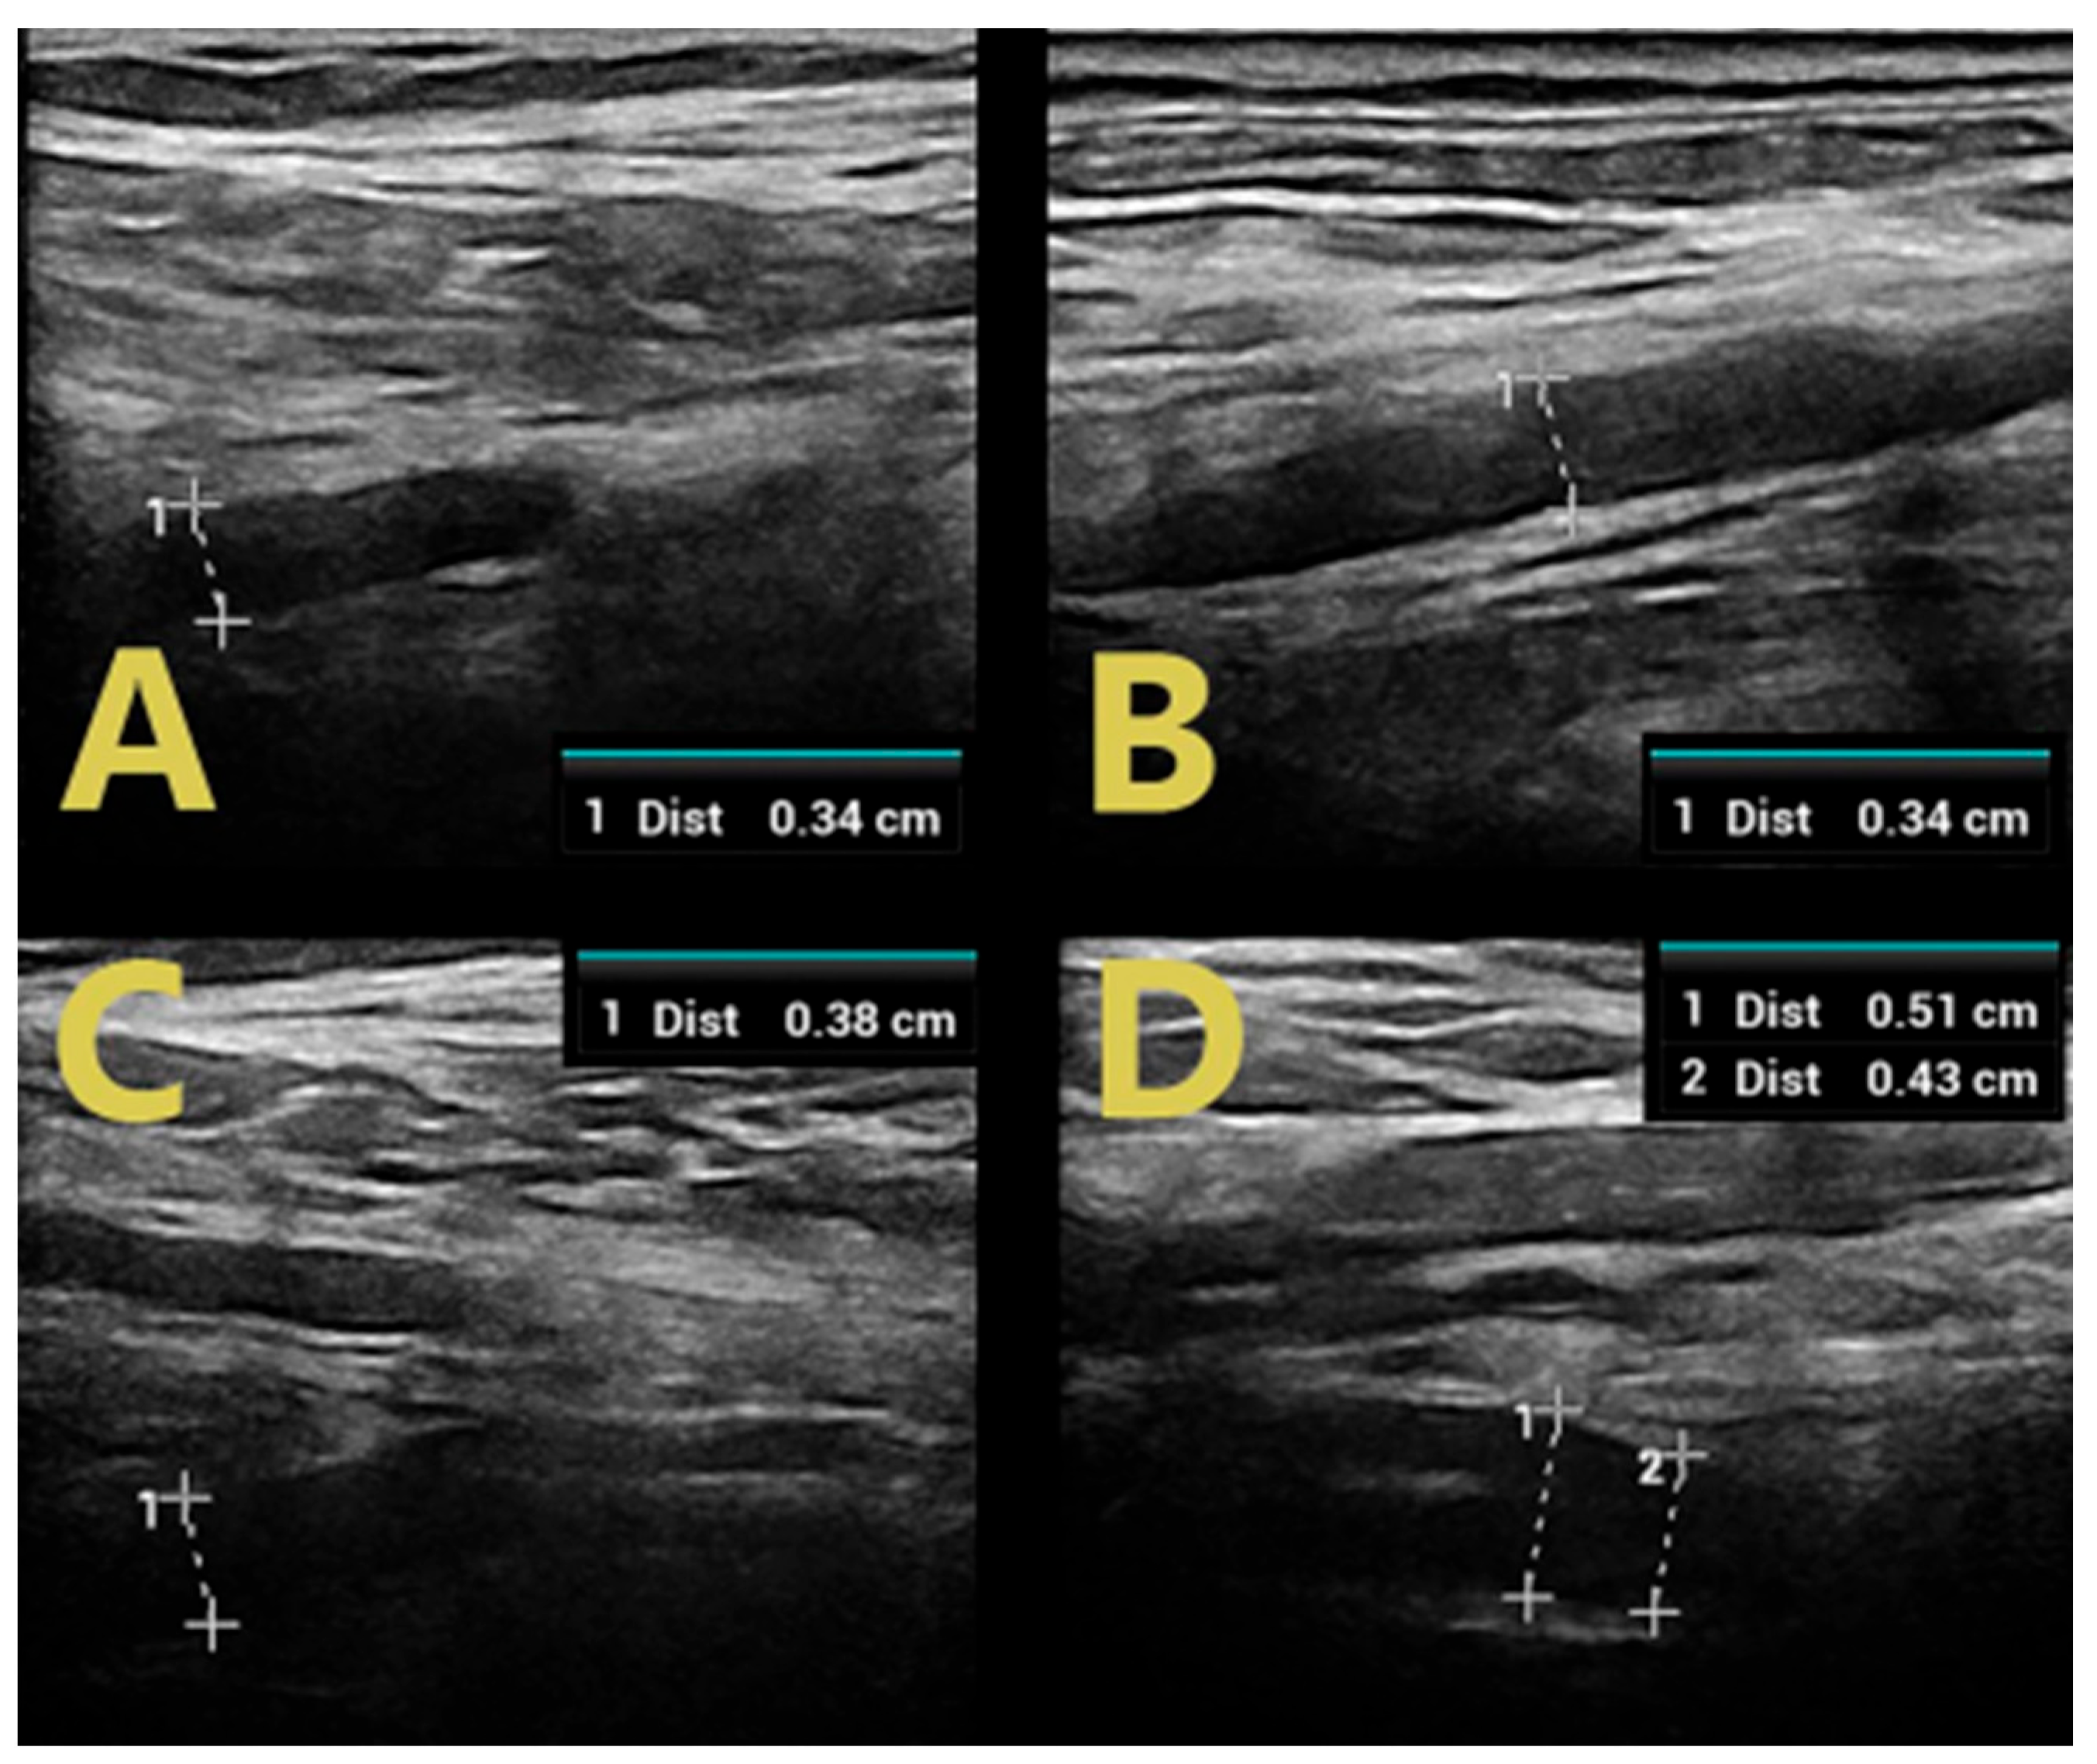

| SM | >6 months | - | 3/5 (ataxia) | ↑ CSA RMN, RUN, SBRRN ↑ C5 LAX CSA ↑↑ C6 | ↑↑ CSA RTN, RPN, ↑ CSA RSN | ↑ duration LMR | ↑ duration RMP |

| LAX CSA ↑ CSA VN | |||||||

| DJ | 17 months | - | 3/5 | ↑↑ CSA LMN ↑ CSA LUN ↑ C5 LAX CSA ↑↑ C6 LAX CSA ↑ CSA VN | ↑↑ CSA LTN, LPN, ↑ CSA LSN | ↑ duration LMM | ↑F latency LMT |

| DR | 6 months | - | 3/5 | ↑↑ CSA RMN ↑ CSA RUN ↑ C5 LAX CSA ↑↑ C6 LAX CSA ↑ CSA VN | ↑ CSA RTN, RPN, RSN | ↑ F latency RMT, LMT | |

| SZ | >5 months | - | 2/5 | ↑ CSA RMN, RUN ↑ C5 LAX CSA ↑↑ C6 LAX CSA ↑ CSA VN | ↑↑ CSA RTN, RPN, RSN | F wave absence RMT, LMP | |

| WJ | 17 months | - | 3/5 | ↑↑ CSA RMN ↑ C5 LAX CSA ↑↑ C6 LAX CSA ↑ CSA VN | ↑↑ CSA RTN, RPN, RSN | ↑ duration RMP, RMT | |

| BA | 6 months | 4/5 | 3/5 | ↑↑ CSA RMN, RUN ↑ C5 LAX CSA ↑↑ C6 LAX CSA ↑ CSA VN | ↑↑ CSA RTN, RPN, RSN | ↑ duration RMU | ↑ duration RMT |

| BD | 14 days | - | 2/5 | ↑ C5 LAX CSA ↑ C6 LAX CSA | ↑ CSA LTN, LPN | ↑ duration RMU, LMP | F-wave absence RMP |

| SMi | 4 days | 4/5 | 2/5 | ↑↑ CSA RMN ↑ C5 LAX CSA ↑ C6 LAX CSA | ↑ CSA RTN, | ↑ duration RMU | ↑F latency RMP, LMP ↑ duration RMP, LMP, RMT |

| LW | 6 weeks | - | 3/5 | ↑↑ CSA RMN, ↑ RUN ↑ C5 LAX CSA ↑ C6 LAX CSA | ↑ CSA RTN, RPN | ||